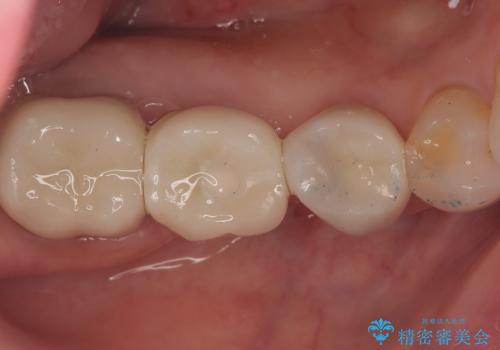

- 主訴:右下のセラミックのブリッジが何度も同じところで折れて壊れてしまう。

対合歯との咬合関係において、右下7番目と6番目の被せものの連結部がたわみやすい環境にあったため、ブリッジの新製ではなくインプラント治療を行いすべての歯を単冠仕上げとすることにしました。

何度も右下6、7間でブリッジが折れてしまうとのことでした。対合歯とブリッジの連結部が強く当たりたわみやすい状態でした。破折しずらい金属を使用したブリッジの選択もありましたが、支台歯(右下7)が失活歯場合、破折リスクが高く、破折してしまった場合にまたブリッジを外しての再治療になってしまう可能性を説明したところ、全て単冠仕上げとできるインプラント治療を希望されました。

右下5番のクラウンは、ブリッジを切断しそのまま使用していただいています。